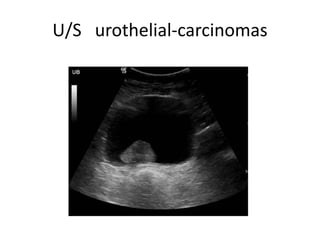

U/S urothelial-carcinomas

urothelial carcinoma. LongitudinalUS image of the bladder shows a large, hypoechoic urothelial carcinoma (arrow) within the bladder.